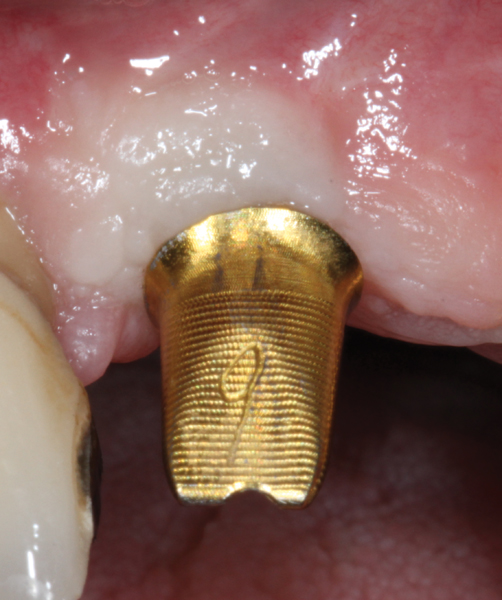

Fig 8. Some implant abutments flare drastically at the connection with the implant. This will compromise blood supply to the area, encroach on the peri-implant biologic width, and likely result in a more apical position of the bone and soft tissue. This design should be modified for use in the esthetic zone.

Figure 8

Fig 9. The flared area is recontoured to a diameter no bigger than that of the implant. This is done preoperatively with a heatless stone wheel and then polished.

Figure 9